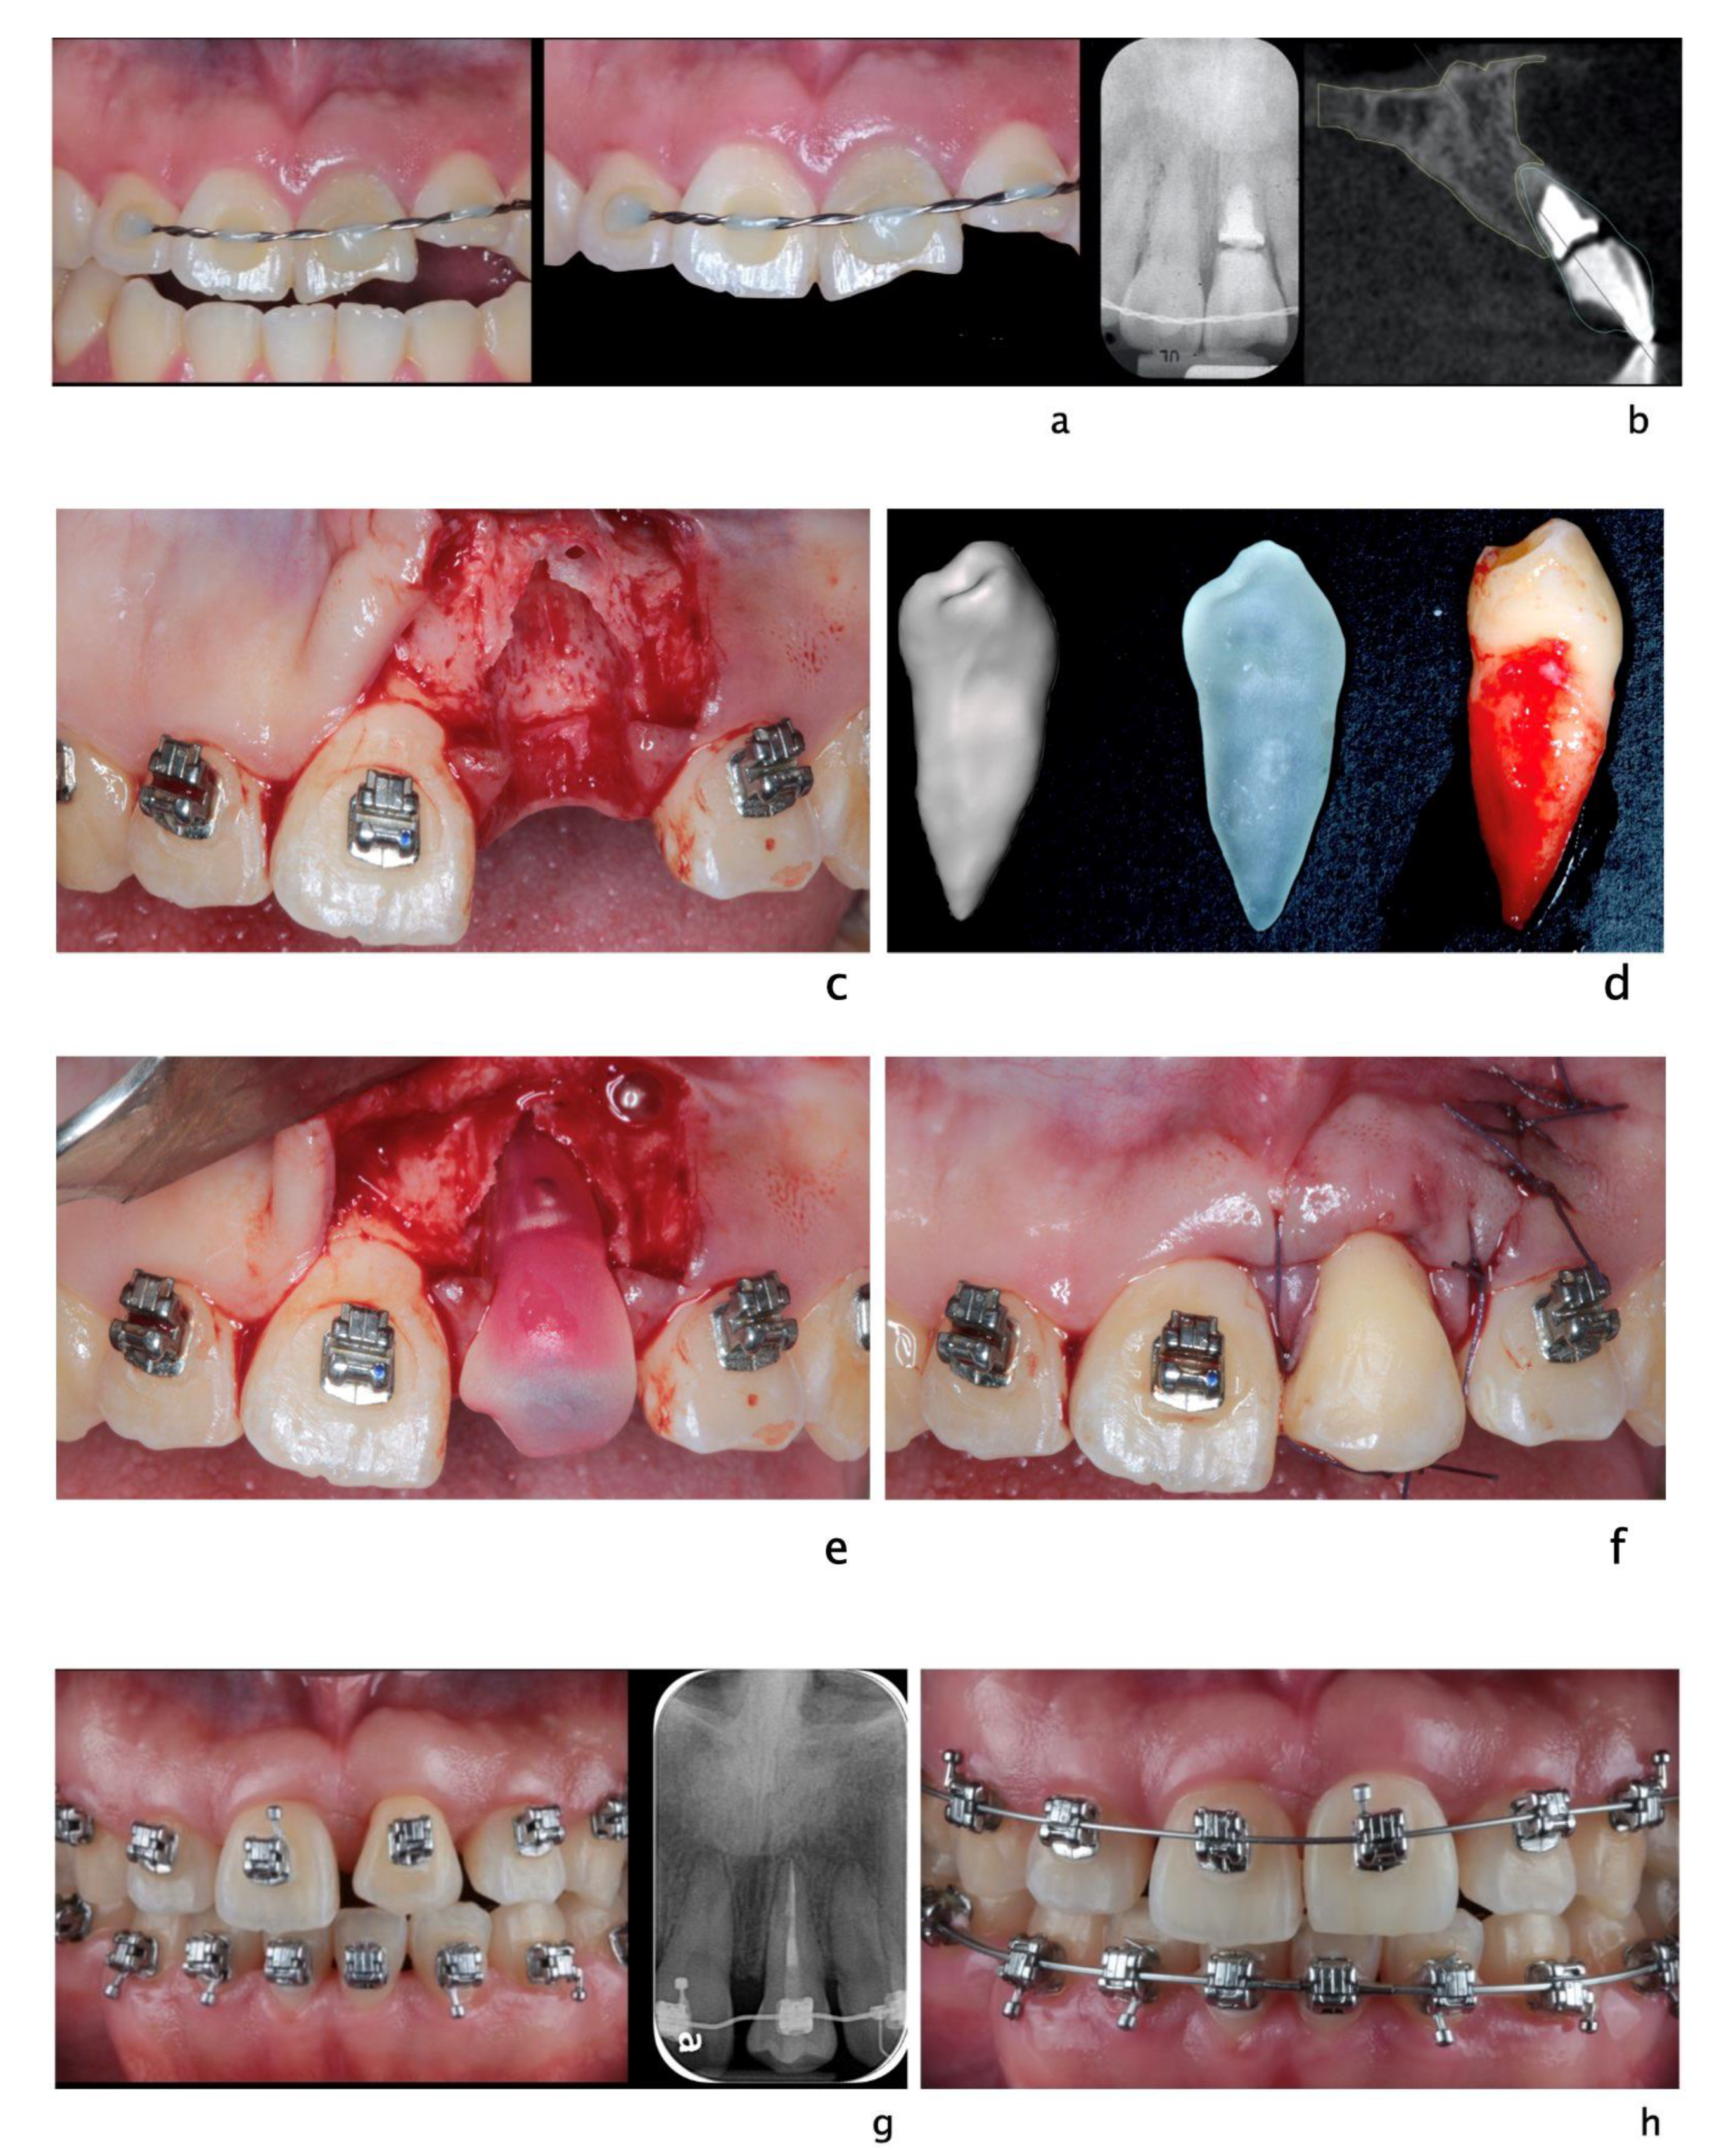

Figure 5.

Clinical scenario of a 17 years-old adolescent hit by a baseball ball in the anterior maxillary region. The boy presented to the Periodontal Department at Tufts University, Boston USA with crown fracture of left central incisor (#9) (a,b). Peri-apical radiograph show apical radiolucency, sign of necrosis. After the diagnosis, CaOH2 was applied. The root canal definitive treatment was completed but after 2 months the patient still presented with a fistula, that was tracked via a gutta-percha point. A CBCT scan was performed in order to diagnose the extent of the peri-apical lesion (c in sequence). The extent of the lesion did not suggest an endodontic therapy revision. Exploratory surgery was performed in order to rule out tooth fracture (d). The apex was resected in order to access the palatal aspect of the tooth. A PA radiograph was taken in order to verify correct apex resection and endodontic retrograde seal (e). Due to active patient skeletal growth, a decision was made to enucleate the endodontic cyst and treat the cavity with bone grafting material, in order to preserve the site for future implant placement (f,g). PA radiograph comparison before and after grafting placement (h,i). The patient was followed up for 2 months, and a fistula was identified apical to #9 (l). Tooth #10 was diagnosed as necrotic. A root canal was performed (m) and the apical radiolucency and fistula were resolved at 1 month follow up (n).